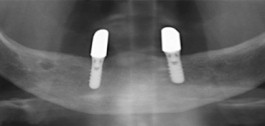

Gelingt es wegen geringer Kieferkammhöhe nicht, mit Totalprothesen einen ausreichenden Halt zu erreichen, so verbessern implantatgetragenene Prothesen den Halt der Prothese deutlich und dauerhaft. Die Implantate (siehe Menüpunkt: Implantologie) sichern durch ein stabiles Verbindungselement oder Halteelement die Befestigung der Unterkieferprothese. Obwohl zwei Implantate oft genügen, empfehlen wir aus statischen Gründen meistens vier Implantate. Die Anzahl der notwendigen Implantate ist auch von der individuellen Situation des Patienten abhängig. Die Nachteile, die durch eine lockere Totalprothese entstehen, sind nach einer Implantatprothetik nicht mehr vorhanden.

Implantatgetragener Zahnersatz

Röntgenaufnahme (Implantate)